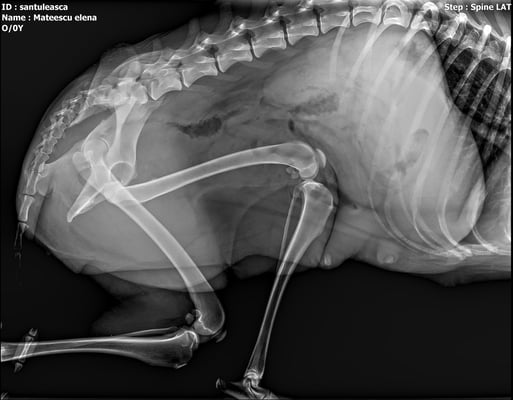

Shanya wurde von einem Auto angefahren und lag dann zwei Tage verletzt im Straßengraben, ehe sich jemand erbarmt hat und Grig um Hilfe bat.

Sie wird voraussichtlich zwei Operationen brauchen, eine davon am Becken, die sehr kompliziert ist. Die Kosten hierfür liegen bei 1500,- Lei = 300,- Euro. Wenn das alles gut überstanden ist, wird sie wahrscheinlich irgendwann eine weitere OP benötigen, um die Metallimplantate wieder zu entfernen. All das kostet leider eine Menge Geld.

Shanya was hit by a car and then lay injured in a ditch for two days before someone showed mercy and asked Grig for help.

She will probably need two surgeries, one of them on the pelvis, which is very complicated. The costs for this are 1500,- Lei = 300,- Euro. If all this is well done, she will probably need another surgery sometime to remove the metal implants again. All this unfortunately costs a lot of money.